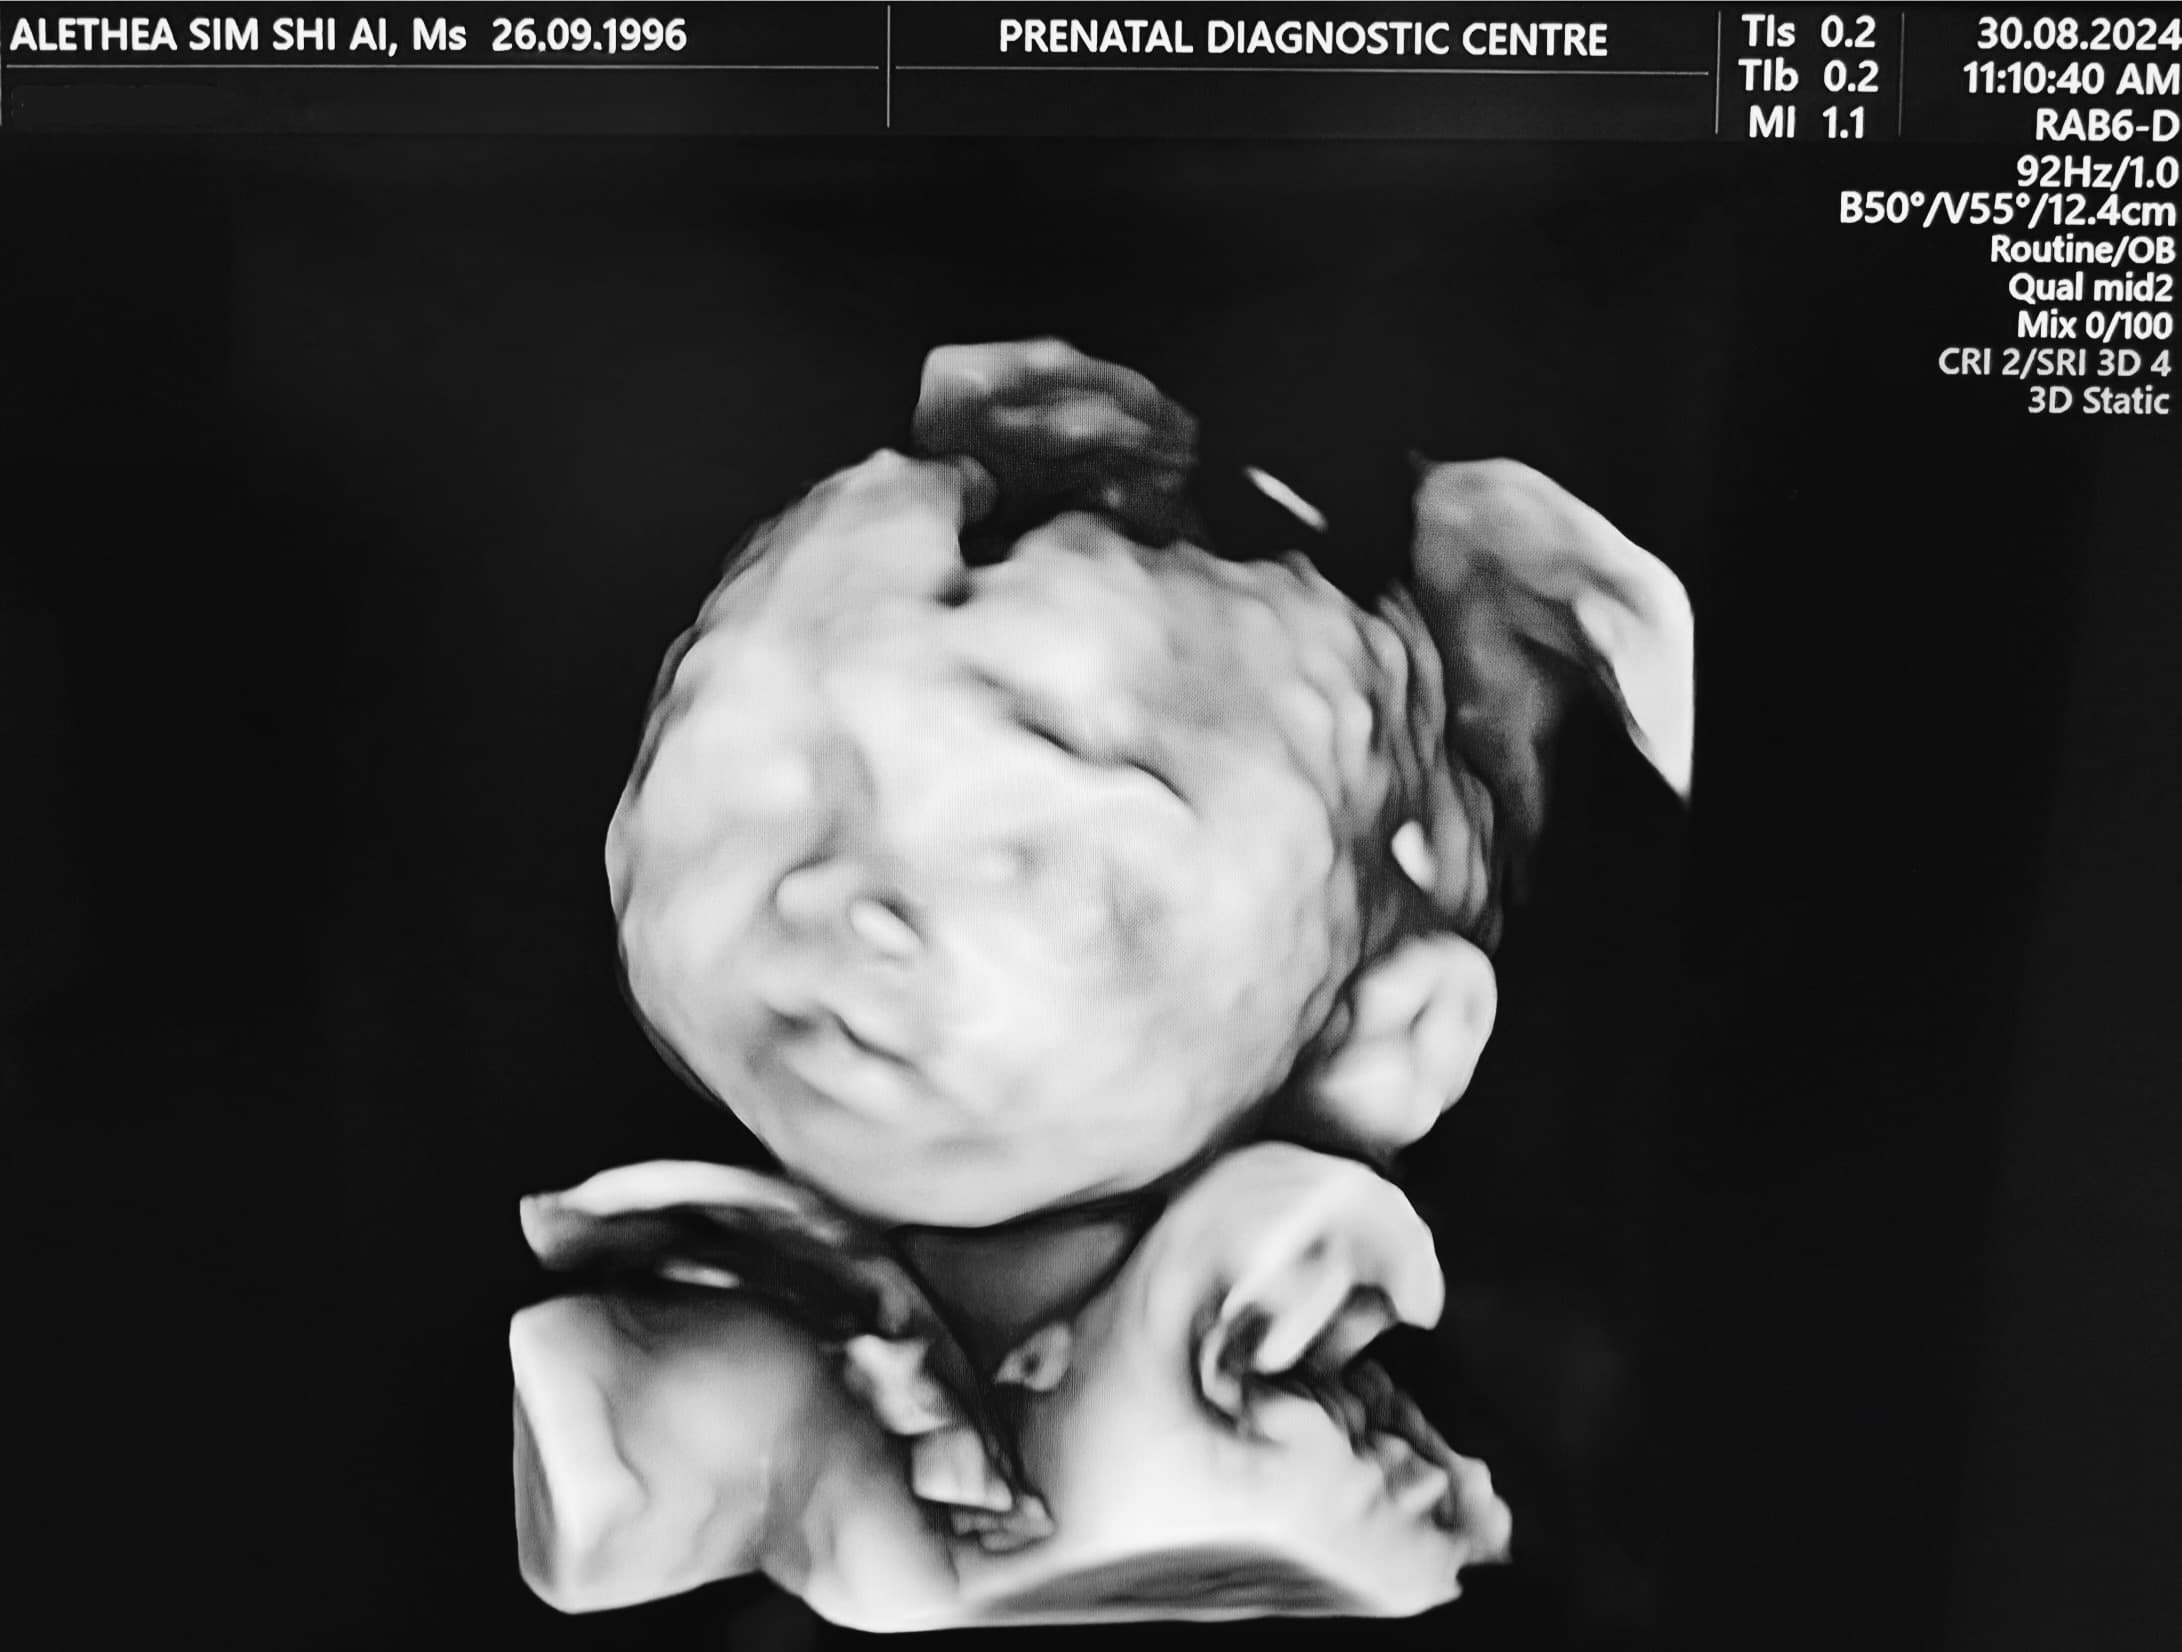

8/30/24

Week 22